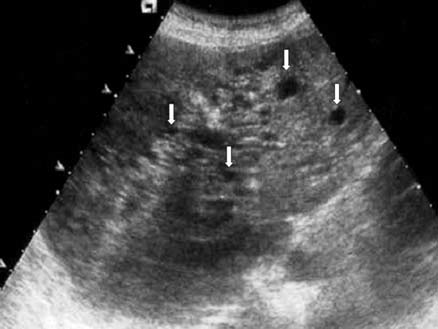

What is Metastatic disease?

This is the most common form of neoplastic involvement of the liver. The primary sites include colon, breast, and lung.

What is the sonographic appearance of Metastatic disease?

Appearance varies

Multiple nodes

Solitary

Well

defined

Echogenic to hypoechoic mass

Homogenous

Calcification

Necrosis

What are the presenting symptoms of Metastatic disease?

jaundice

hepatomegaly

weight loss

decreased appetite

What are the lab values that would suggest Metastatic disease?

Abnormal LFT